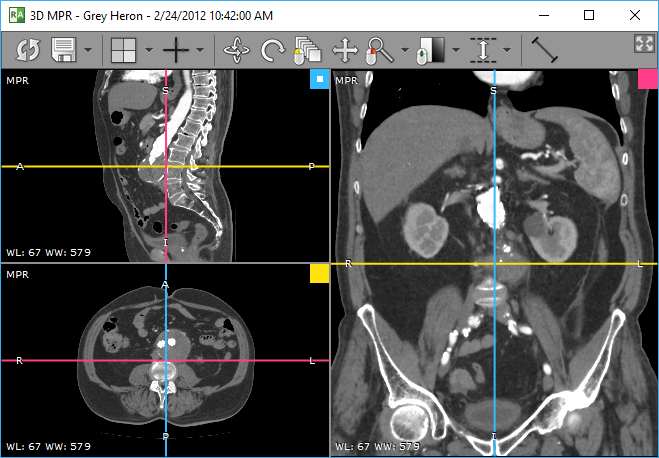

RadiAnt DICOM Viewer 内置的 3D MPR 工具可在任意平面(斜面)上重建图像,帮助实现仅凭基础图像无法实现的解剖结构可视化。

2. 序列加载到内存并完成预处理后,3D MPR 视图将在新窗口中显示。在较慢的系统上,此过程可能需要几秒钟。